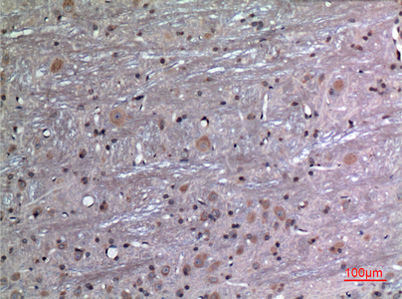

Product name: FGF-12 rabbit pAb

Dilutions: Western Blot: 1/500 - 1/2000. IHC-p: 1:100-300 ELISA: 1/20000. Not yet tested in other applications.

Immunogen: The antiserum was produced against synthesized peptide derived from the Internal region of human FGF12. AA range:31-80